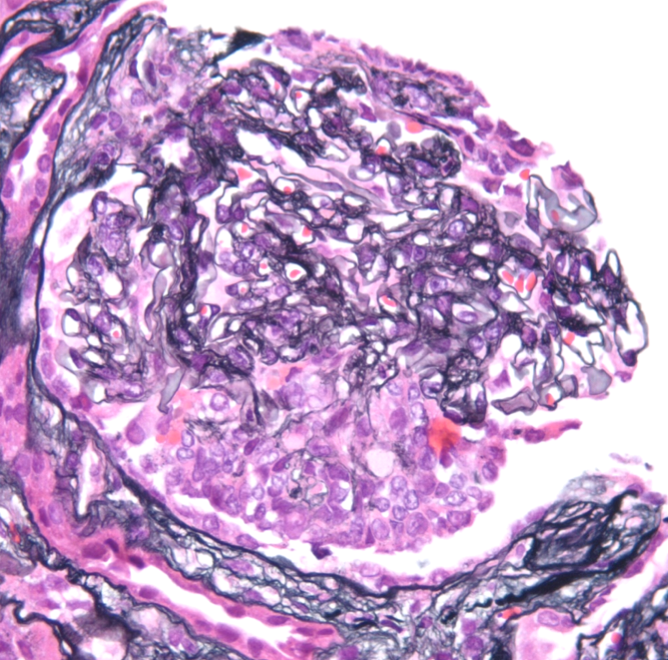

Light microscopy

A spectrum of findings can be present by light microscopy. Most cases show a mesangioproliferative pattern of injury characterized by hypercellularity in the mesangium. A subset of cases will additionally show endocapillary hypercellularity, frequently including neutrophils within the glomerular capillaries similar to the exudative changes seen in post-infectious glomerulonephritis. Cases with endocapillary hypercellularity may also be associated with crescentic injury. An additional subset of patients show a membranoproliferative (MPGN) pattern of injury, including mesangial hypercellularity and duplication of the glomerular basement membranes with or without endocapillary hypercellularity and crescents. The tubulointerstitium will show variable degrees of fibrosis and atrophy. Thrombotic microangiopathy has rarely been observed in the setting of C3GN, likely related to the common pathophysiology of APC dysregulation.